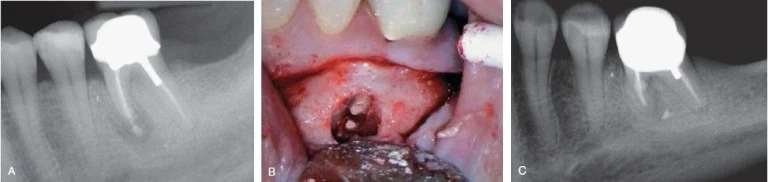

Hình 8. Khi nghi ngờ nứt dọc chân răng, đôi lúc phải lật vạt để quan sát tốt hơn.

Hình 10. Nứt dọc chân răng dẫn đến chia đôi chân răng, điều này có thể phát hiện dược trên X quang

Hình 11. Mặc dù nứt dọc chân răng không phải lúc nào cũng thấy được trên X quang nhưng với một góc chụp đúng thì có thể quan sát rõ đường nứt.

Hình 16. Khi có khoảng trống giữa chất trám bít ống tuỷ và thành ống tuỷ thì nghi ngờ cao có chia chân răng.